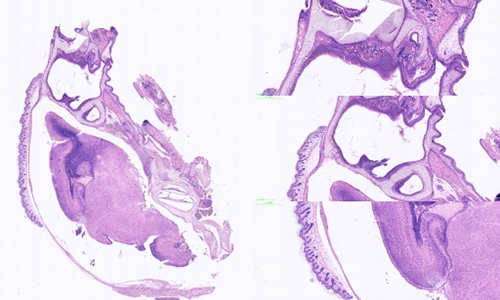

冰冻切片和石蜡切片是常见的组织学研究中的两种切片技术,它们在样本处理和切片制备过程中存在一些区别。

扫描切片

切片质量方面:冰冻切片相对于石蜡切片来说,切片质量可能稍差。由于冰冻切片的过程较快,切片的质量受到冷冻状态的影响,容易出现组织断裂、伪影和冰晶等问题。而石蜡切片在固定和浸泡处理后,组织样本得到更好地保护,切片质量相对较好。

切片的用途方面:冰冻切片主要用于快速初步观察和诊断,例如快速冰冻切片可以用于术中病理诊断。而石蜡切片则适用于各种组织学研究,包括光镜下观察、免疫组化染色和分子生物学研究等。

冰冻切片石蜡切片是两种常见的组织学切片技术,选择合适的切片技术取决于研究的目的、组织类型以及需要的切片质量。无论是冰冻切片还是石蜡切片,它们都为组织学研究提供了重要的工具和手段。